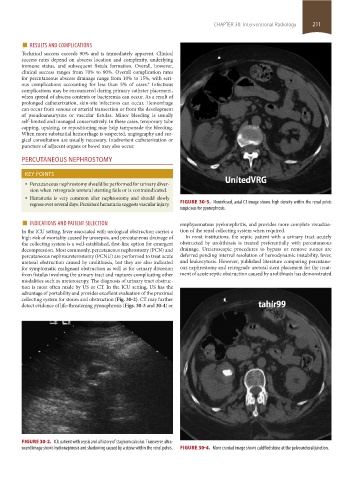

regress over several days. Persistent hematuria suggests vascular injury. FIGURE 30-3. Noninfused, axial CT image shows high density within the renal pelvis

suspicious for pyonephrosis.

collecting system for stones and obstruction (Fig. 30-2). CT may further

detect evidence of life-threatening pyonephrosis (Figs. 30-3 and 30-4) or

FIGURE 30-2. ICU patient with sepsis and a history of staghorn calculus. Transverse ultra-

sound image shows hydronephrosis and shadowing caused by a stone within the renal pelvis. FIGURE 30-4. More craniad image shows calcified stone at the pelvoureteral junction.